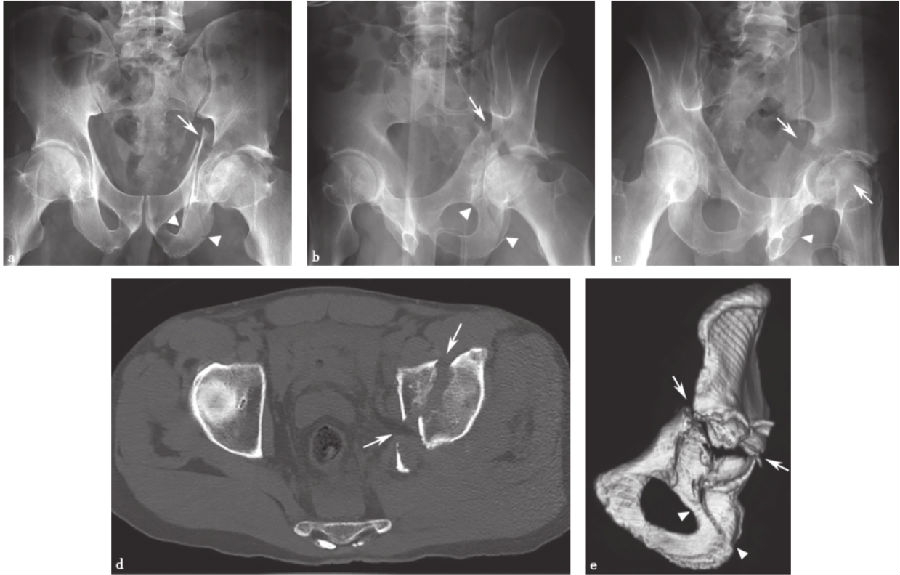

1、双柱髋臼骨折:

双柱髋臼骨折(图9-10)包括前柱和后柱,并延伸到闭孔环和髂骨翼,是最常见的髋臼骨折之一。在X线片上,前柱和后柱的骨折受累特征分别是髂耻线和髂坐线的破坏。然而,这些线的破坏也可能出现在其他骨折模式(例如横行骨折)。闭孔环和髂骨受累也必须存在,作为双柱髋臼骨折分型。在前后位X线片上,髂骨翼的骨折延伸并不总是很明显;但在倾斜的Judet位或CT上常常可以被发现。

图9 双柱髋臼骨折a.骨盆正位片;b、c.双侧斜位骨盆X线片;d.轴位CT扫描;e.矢状面重建CT扫描。直线箭头:髋臼骨折;箭头:闭孔环中有破裂;弯曲的箭头:骨折延伸到髂骨翼。

图10 双柱髋臼骨折并有spur征a.闭孔斜位X线片;b.轴位CT图像显示骨折标志(直线箭头),代表骨折移位涉及坐骨支(直线箭头)。请注意,坐骨支(箭头)不再连接髋臼的负重部分。

在CT上,可以看到前柱和后柱的骨折受累,骨折可能呈粉碎性。闭孔环的断裂破坏具有可变的外观,耻骨上支的骨折可能发生在耻骨髋臼连接处。另外,如果不移位,可能难以确定耻骨下支的骨折。主要骨折线从髋臼向髂骨翼延伸,特征在于冠状面上。

如果存在的话,双柱断裂的特征性标志是“刺征(spur)”标志(又称“马刺征或枪刺征”)(图10a、b)。这个标志代表了髂骨翼骨折的坐骨支撑的后位移,这实质上将髋臼的顶部与轴骨骼断开。当发生这种情况时,躯干和上身的重量将不再受髋臼支撑。在X线片和CT影像中,骨折标志表现为在上髋臼水平向后延伸的骨碎片。连续CT图像的评估显示骨折,将坐骨神经与髋臼顶分开。